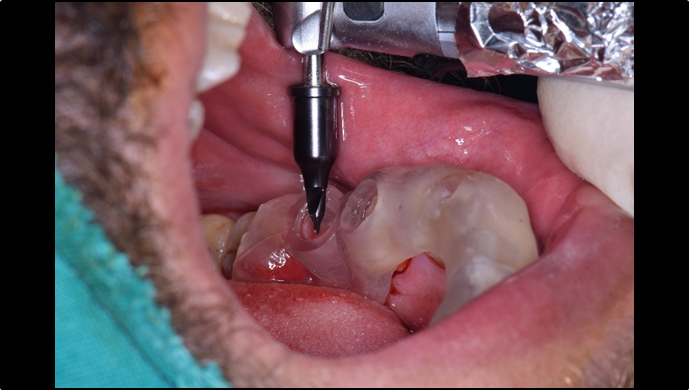

Clinical case: EImmediate implant placement & loading of #35 extraction socket with defect

- Courtesy of Dr. Kwang Bum Park, Korea -